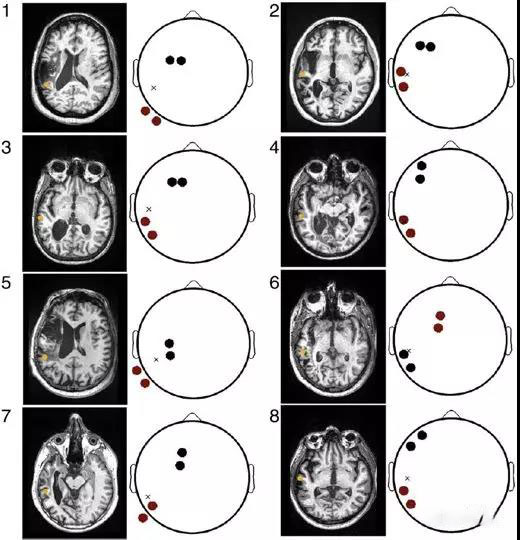

个体化的刺激增加在中风患者中的靶向电流强度

每个中风患者的电极蒙太奇位置(尽管只使用了两对电极)

与常规刺激蒙太奇相比,目标位置(黑圈)的平均电流增加64%